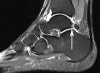

MRI : 발목 충돌증후군(Posterior impingement)

MRI에서 경도의 관절액 저류와 활막 증식이 확인될 수 있습니다.